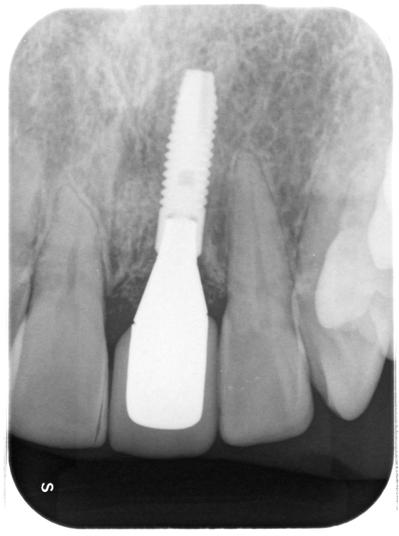

前歯部へのインプラント治療。

外傷=転倒による歯牙破折により抜歯。

使用インプラントはアストラ(スウェーデン)。

以前にも紹介したが、外傷により歯牙破折、抜歯を余儀なくされ、患者さんはインプラント治療を希望された。

しかしながら、歯牙の位置が悪く、安直にインプラント治療行うべきケースではなかった。